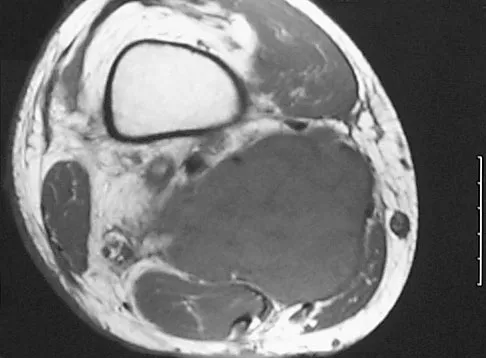

Question 7 High Yield

A 45-year-old woman has had radiating pain in the medial ankle for the past 3 months. Examination reveals a small mass in the retromedial ankle region and a positive Tinel's sign. An intraoperative photograph and a hematoxylin/eosin biopsy specimen are shown in Figures 24a and 24b. Treatment should consist of

Detailed Explanation